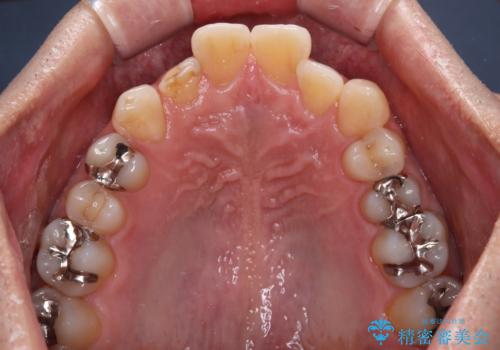

- 内側に倒れている前歯が擦れてしみるとのことで来院された患者様です。

削れていた部分は詰め物が入っていましたが、縁の部分がしみているようで、変色も目立っていたため、オールセラミッククラウンにて補綴治療を行うこととしました。